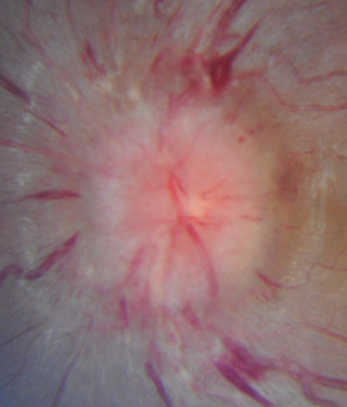

Grade 5

5: With grade 5 edema, the nerve is so swollen that all the normal features are obscured. You can't really see any of the blood vessels or anything else.